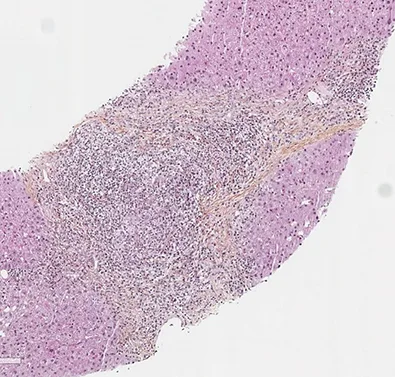

Les patients suivis pour une CBP peuvent présenter des degrés variables d’inflammation hépatique mais habituellement, dans la CBP, on retrouve très peu d’hépatite d’interface ou d’hépatite lobulaire. Environ 8 à 10 % des patients CBP vont présenter des lésions hépatiques faisant évoquer une HAI associée (1, 2). Le syndrome de chevauchement CBP+ HAI peut être présent d’emblée dès le diagnostic initial de la CBP dans 60 % des cas mais les patients CBP peuvent également, dans 30 % des cas, présenter une HAI dite secondaire apparaissant parfois plusieurs années après le diagnostic. Les patients HAI peuvent présenter dans 10 % des cas une CBP dite secondaire (figure 1) (3). Dans le cadre d’une CBP, une augmentation anormalement élevée des transaminases (> 5N) et des IgG (> 20 g/l) doit faire suspecter une HAI associée (4). Des anticorps anti- muscle lisse de spécificité anti-actine et des anticorps anti-ADN double-brin peuvent être présents dans 10 % des cas de CBP. Leur présence doit également faire suspecter l’existence d’un syndrome de chevauchement CBP+ HAI. Dans une étude s’intéressant aux anticorps anti-ADN double brin, ceux-ci étaient présents chez 60 % des patients CBP+ HAI, mais seulement chez 4 % des patients CBP et 26 % des patients HAI (p<0,0001 et 0,01 respectivement). La double positivité d’anticorps anti-ADN double brin et d’anticorps anti-mitochondries était présente chez 47 % des patients CBP+ HAI, mais seulement chez 2 % des pathologies contrôles (5). Dans une autre étude, la présence d’anticorps anti-ADN double brin, une augmentation des ALAT et des IgG étaient les trois facteurs significativement associés aux CBP+ HAI (6). De plus, chez les patients CBP non répondeurs à 12 mois à l’acide ursodésoxycholique (AUDC), une HAI doit être systématiquement recherchée. La présence d’un seul élément évocateur d’HAI n’est en revanche pas suffisant pour poser le diagnostic de syndrome de chevauchement. La réalisation d’une biopsie hépatique, en l’absence de contre-indication, est nécessaire pour confirmer le diagnostic de CBP+ HAI. La présence d’une hépatite d’interface et/ou d’une hépatite lobulaire, bien que non spécifiques, et son intensité permet de confirmer la présence d’une HAI. Le score histologique « modified HAI » (mHAI) développé par Ishak et al. permet de décrire l’activité hépatique inflammatoire et définit les indications de traitement (7, 8). Ce score décrit 4 catégories d’inflammation nécrotico-inflammatoire : l’hépatite d’interface périportale, la nécrose confluente, l’inflammation lobulaire et l’inflammation portale (figure 2). Un score mHAI> 4 est une indication de traitement immunosuppresseur. Les critères de Paris définis par Chazouillières et al. sont cependant les plus couramment utilisés et recommandés par la société européenne pour l’étude du foie (EASL) pour poser le diagnostic de syndrome de chevauchement CBP+ HAI. Ils reposent sur la présence d’au moins deux critères sur trois de CBP : PAL> 2N ou GGT> 5N ; anticorps anti mitochondries≥ 1/40 ; lésions biliaires florides à l’histologie et d’au moins deux critères sur trois d’HAI : ALAT> 5N ; IgG sériques> 2N ou présence d’anticorps anti muscle lisse ; une hépatite d’interface modérée à sévère en histologie (tableau 2, figure 2) (1). Dans une étude publiée en 2010, la sensibilité et la spécificité des critères de Paris pour diagnostiquer une CBP+ HAI étaient respectivement de 92 % et 97 % (9). Le score de Paris est un score différent de ceux utilisés pour faire le diagnostic de chaque pathologie propre CBP ou HAI. Le groupe de travail international de l’HAI ne recommande pas l’utilisation des scores diagnostiques habituels d’HAI (corrigés ou simplifiés) pour faire le diagnostic de CBP+ HAI du fait de leurs très faibles sensibilité et spécificité (9-12). L’objectif de poser un diagnostic de syndrome de chevauchement, et de manière précoce, est de pouvoir proposer un traitement adapté, notamment immunosuppresseur afin d’éviter la progression de la fibrose. Néanmoins, il est important de ne pas porter de diagnostic par excès afin d’éviter aux patients des effets secondaires d’une corticothérapie et/ou d’un traitement immunosuppresseur qui peuvent être sévères.

Figure 2 : Lésions histologiques biliaires évocatrices de CBP (A, B, C), lésions histologiques d’hépatite d’interface et d’hépatite lobulaire évocatrices d’HAI (D, E, F).